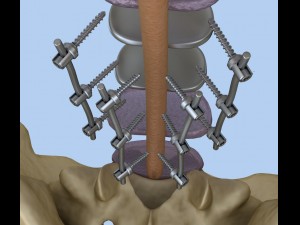

spinal fixation system - titanium bracket 3D 모델

spinal fixation system - titanium bracket. human spine, spinal cord, sacrum and fixation system medically accurate high quality 3d model.

hi-poly 3d model of human spine with internal structure.

spine fixation spinal cord screw surgery system anatomy backbone bone brace bracer bracket column disc paralyze titanium treatment vertebra이 아이템에 대한 코멘트 없음.